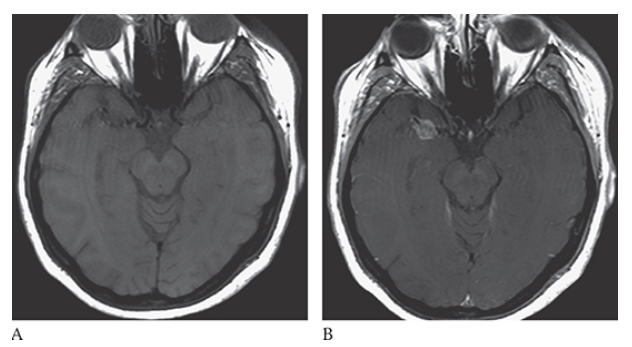

Acoustic Neuroma. Noncontrast T1-weighted axial image demonstrating round isointense mass at the left cerebellopontine (CP) angle.

Acoustic Neuroma. Postcontrast T1-weighted axial image demonstrating an intense contrast enhancing extraaxial mass at the left cerebellopontine angle close to the left internal auditory canal (IAC) consistent with an acoustic neuroma.